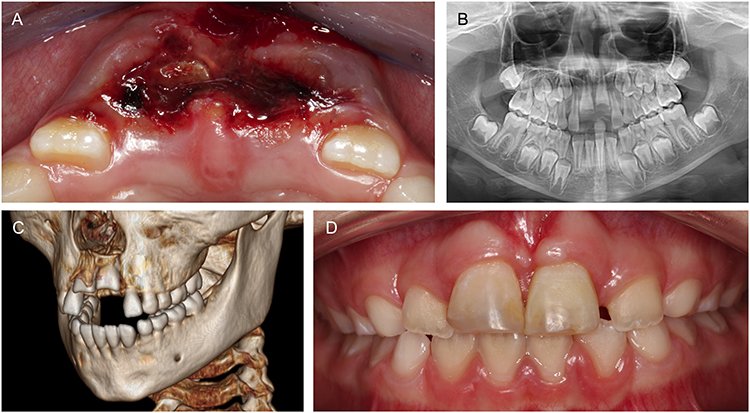

Starke Denudationen, wie sie bei Intrusionen auftreten, oder desmodontale Schäden durch trockene oder falsche Lagerung nach Avulsionen, können daher zu einer Ersatzresorption und schließlich zur Ankylose des Zahnes führen (Abb. 2A bis C), wobei das Dentin irreversibel abgebaut und durch Knochen ersetzt wird [30,31]. Ankylosierte Zähne weisen eine reduzierte Beweglichkeit und einen metallischen Klopfschall auf und neigen mit fortschreitendem Knochenwachstum zur Infraposition (Abb. 2D).

Prof. Dr. Widbiller